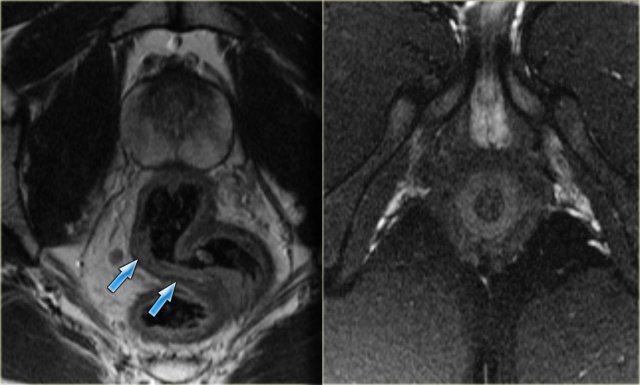

Perianal fistula: axial T2WI without fatsat (left) and with fatsat (right) Perianal fistula: axial T2WI without fatsat (left) and with fatsat (right)

T2W images without fatsat better display the anatomy, while the fatsat images better depict the fistulas.

On the left axial T2W images with and without fat saturation.

An intersphincteric fistula is located at 6 o'clock.

Continue with coronal images.

On the coronal image the fistula runs caudally towards the skin.

There is no connection with the external sphincter.